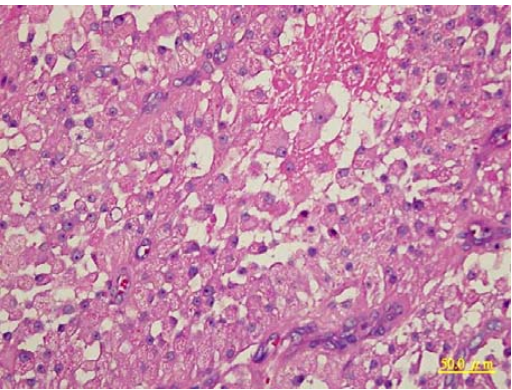

27.狗肛門周區發現柔軟之腫塊,其外觀特徵及組織病變如下圖所示,則其診斷應為:

(A)鱗狀上皮細胞癌(squamous cell carcinoma) (B)皮脂腺瘤(sebaceous gland adenoma) (C)圍肛腺瘤(perianal gland adenoma) (D)毛囊上皮細胞瘤(trichoepithelioma)